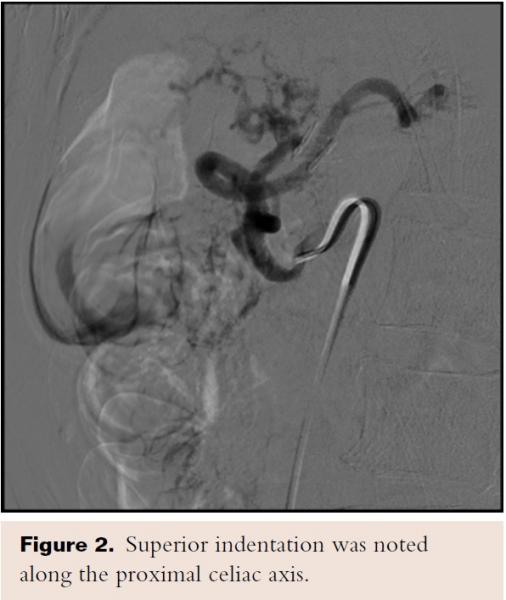

An upper endoscopy showed erosive gastritis in the antrum and body of the stomach, and a 6 mm polyp in the cardia. Cultures were negative for H pylori. Colonoscopy showed sigmoid diverticulosis. A CT angiogram of the abdomen showed atherosclerotic disease of the abdominal aorta without aneurysmal dilatation. Hard and soft plaques were present at the celiac axis origin and there was an atypical course of the celiac axis with focal narrowing 75% at the inferior aspect of a vertically directed proximal portion and distal mild dilatation, which is most compatible with the appearance of compression by the median arcuate ligament. Superior and inferior mesenteric arteries and renal arteries demonstrated mild atherosclerotic disease, with calcifications that were negative for focal high-grade narrowing (Figure 1).